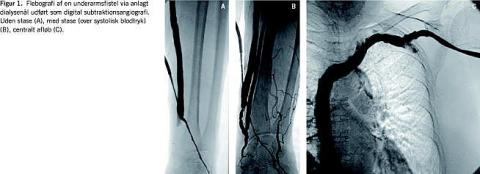

Fistulografi udførtes via et indstik i afløbsvenen (Figur 1A ) efter anlæggelse af en blodtryksmanchet centralt for indstiksstedet, der var pumpet op til et tryk over det systoliske. Efter kontraststofinjektion retrogradt i fistlen visualiseredes anastomosen mellem venen og arterien (vinduet) (Figur 1 B). Herefter fjernedes trykket i manchetten, og resten af afløbet visualiseredes helt ind til højre atrium (Figur 1C). Hvis vinduet var mangelfuldt fremstillet trods stase, blev der suppleret med ultralydsskanning. I tilfælde af stenose(r) (> 50% sammenlignet med tilstødende karsegment med normal diameter) eller okklusion af fødearterien, vinduet eller afløbsvenen henvistes patienten til PTA.